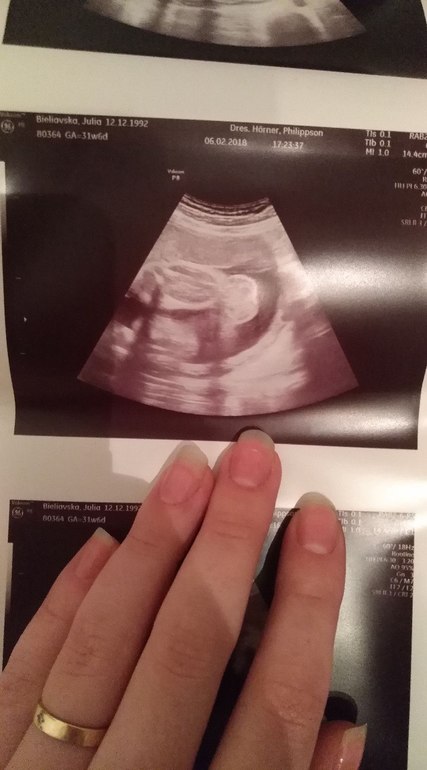

III скрининг, 32 неделя подходит к концу, жидкость в почках

На консультации в ЖК, выбор женской консультации/гинекологаНачнем с веселого! Третий скрининг позади, осталось совсем чуть-чуть ☺️. ИИИИ наша девочка отрастила ЯЙЦА! 🤣. Таким образом Алиса превратилась в Яна! Но это не точно...! 😁 хотя судя по фото.... как думаете? Врач сказала что это яички, но писюнчика так и не нашла.

А теперь о плохом. У малыша в почках обнаружили жидкость. Меня то успокоили что это может ничего особо не значить, но для верности направили к более узкому специалисту в другую клинику. 😐

Может было у кого такое - Гидронефроз...? Размер лоханок (надеюсь я правильно использую этот термин) 0,51см и 0,46см.